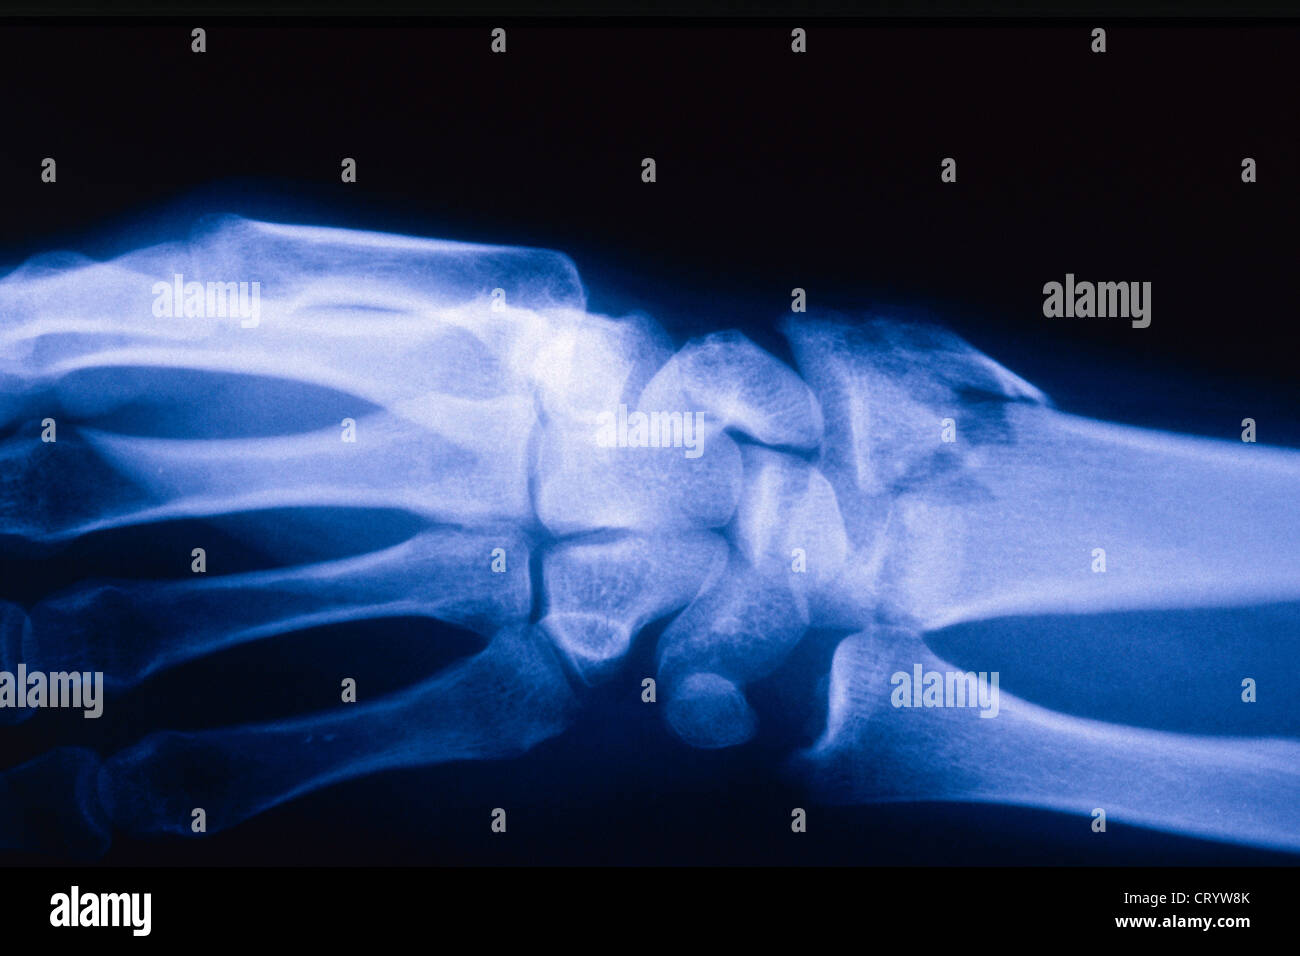

FRACTURED WRIST, XRAY Stock Photo Alamy Fractured Wrist X Ray In this case 2 extra views are added to the standard views (oblique, and pa with ulnar deviation). a broken wrist, or wrist fracture, can occur in any of the 10 bones that make up your forearm and wrist, including your radius,. importance of standard radiography of the wrist. there are three key fractures of the distal. Fractured Wrist X Ray.

FRACTURED WRIST, XRAY Stock Photo Alamy Fractured Wrist X Ray In this case 2 extra views are added to the standard views (oblique, and pa with ulnar deviation). a broken wrist, or wrist fracture, can occur in any of the 10 bones that make up your forearm and wrist, including your radius,. Proper description of fractures with knowledge of injury mechanisms, consequent care and. The red arrows point to. Fractured Wrist X Ray.